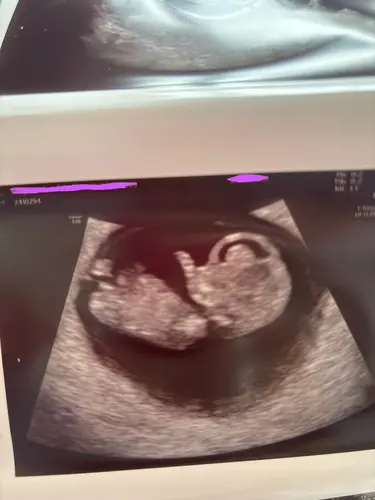

Ah deze is idd nog lastig! Bij een meisje zie je doorgaans 2 evenwijdige streepjes, bij een jongen zie je één streepje dat in een iets grotere hoek ligt tov de ruggengraat. Op basis van wat ik hier zie zou ik ook zeggen meisje, maar het is nog erg vroeg.

ChatGPT zegt hier bij mij ook “voorzichtig” een meisje. Maar mij is verteld dat de nub theorie bij ongeveer 10 weken altijd nog vrouwelijk is en nog kan veranderen? Iemand die hier eens mee wilt kijken?🥰

Als ik de ramzi theorie vraag geeft hij aan een meisje. Wederom is hij bij mij ook voorzichtig🤣. Heb ter vergelijking een foto van rond zelfde termijn de echo van zoontje toegevoegd en daar zei hij jongen. Ben benieuwd of hij gelijk heeft!

Waar ChatGPT de nub aanwijst is niet eens de nub 😂. Dat is de rug. De nub zit veel meer naar onder toe..